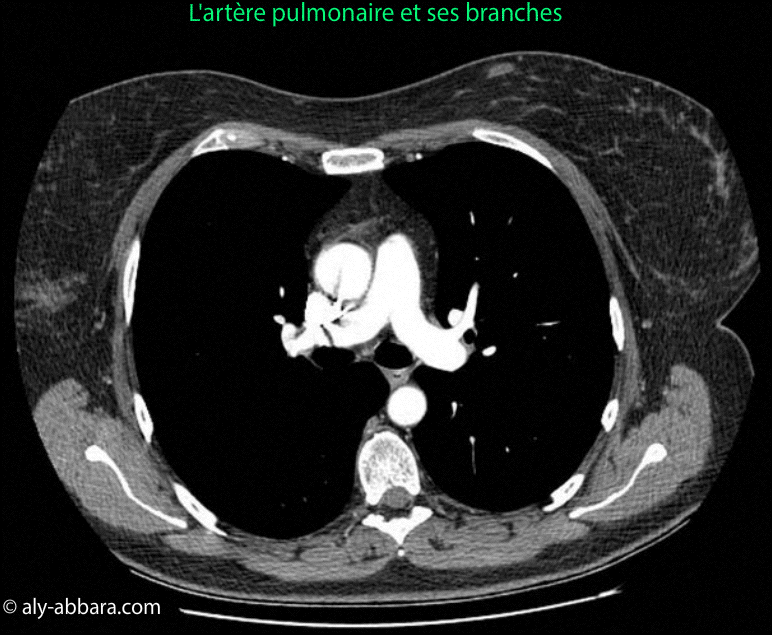

l'artère pulmonaire et ses branches

Images-scanner montrant l'artère pulmonaire et ses branches, puis les

rapports anatomiques de ces vaisseaux avec les organes avoisinants.